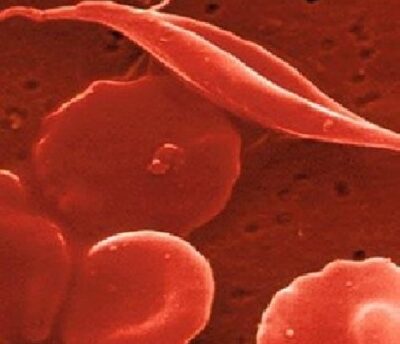

“L’ anemia falciforme è una forma ereditaria di anemia in cui il numero di eritrociti circolanti nel sangue è così basso da non garantire un adeguato trasporto dell’ossigeno in tutto l’organismo. È chiamata “falciforme” per la particolare forma strutturale dei globuli rosi che non sono tondeggianti, biconcave ed elastiche, ma assumono una forma di falce, tendono ad aggregarsi e sono fragili e spigolose.

L’emoglobina fetale è presente nei neonati fino a circa 6 mesi e poi viene sostituita dall’ emoglobina adulta. I bambini con anemia falciforme producono una forma difettosa di emoglobina adulta che porta i globuli rossi a diventare a forma di falce e rimanere bloccati nei vasi sanguigni, causando sintomi dolorosi e altri sintomi. Nella beta talassemia, i pazienti semplicemente non producono abbastanza emoglobina, diventano anemici e sviluppano altre gravi complicazioni.